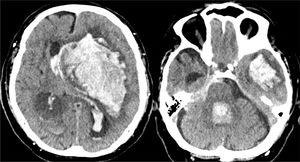

Caso 3Varón de 79 años con pérdida brusca de consciencia en su domicilio. Los servicios de emergencia objetivan un GCS de 4 (O1, V1, M2), pupilas arreactivas y presión arterial de 205/115mmHg. Se procede a realizar intubación traqueal y traslado al hospital; en Urgencias obtiene un GSC de 4 y ausencia de reflejos fotomotor, corneal y oculocefálico. La TC craneal mostró un hematoma intraparenquimatoso en los ganglios de la base derechos, desplazamiento de la línea media e invasión del sistema ventricular (fig. 6). Valorado por Neurocirugía y Neurología, se descartó cualquier tipo de tratamiento. El CT planteó a la familia la posibilidad de la donación de órganos, aceptando esta el ingreso en la UCI para facilitar la donación en ME. A las 48h el paciente se mantenía en coma arreactivo, sin reflejos fotomotor, corneal ni oculocefálicos, pero con persistencia del reflejo tusígeno y de respiración espontánea. La familia no deseaba prolongar más la situación, por lo que se decidió la retirada del soporte ventilatorio. Se les planteó entonces la opción de la donación en asistolia controlada, que autorizaron. Se realizó extracción de riñones y córneas. Los riñones fueron trasplantados, presentando función renal inmediata y buena evolución posterior.